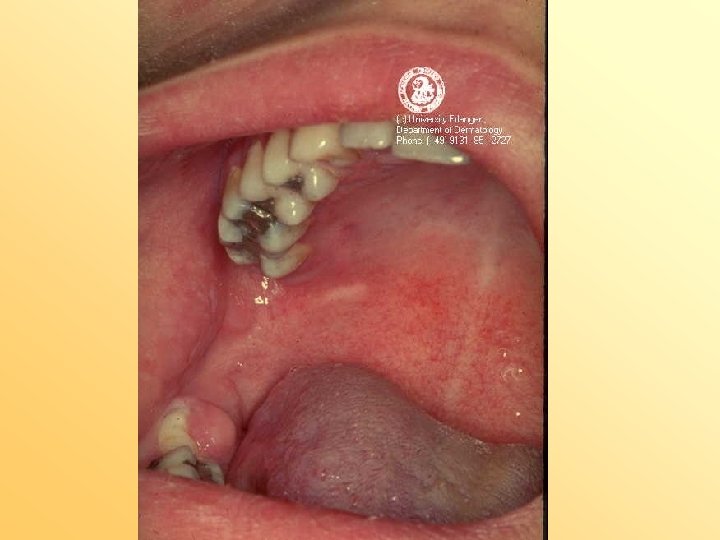

spruw • leeftijd alle leeftijden maar vooral bij: • zuigelingen • meer bij fopspeendragers • bij antibioticagebruik • oorzaak – Candida( gist)

• kenmerken – wit beslag op tong – witte tekeningen op het mondslijmvlies – ontstaat vaak na inname van anitbiotica • behandeling – daktarin orale gel – nystatine druppels